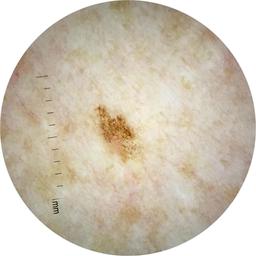

ISIC_5852089

Clinical

| image_type | dermoscopic |